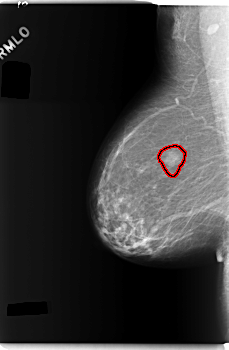

RIGHT_MLO LINES 5944 PIXELS_PER_LINE 3880 BITS_PER_PIXEL 12 RESOLUTION 50 OVERLAY

FILE: C_0275_1.RIGHT_MLO.OVERLAY

TOTAL_ABNORMALITIES 1

ABNORMALITY 1

LESION_TYPE MASS SHAPE OVAL MARGINS ILL_DEFINED

ASSESSMENT 4

SUBTLETY 4

PATHOLOGY BENIGN

TOTAL_OUTLINES 1

BOUNDARY